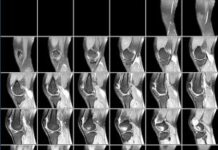

Что покажет МРТ коленного сустава?

МРТ коленного сустава – высокоинформативный метод обследования, который позволяет выявить патологические изменения в мягких тканях.

Компьютерная томография дает возможность получить информацию о структуре и размерах...